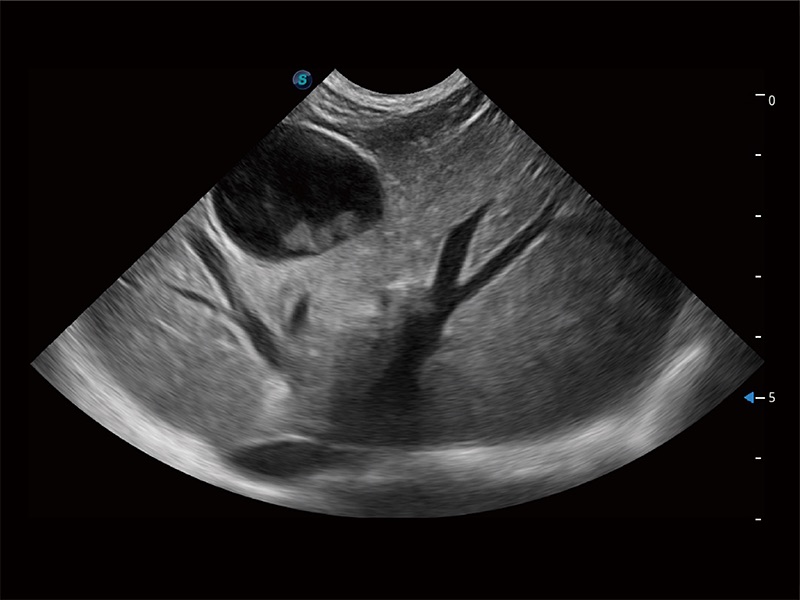

動物是人類最親密的朋友和最值得信賴的伙伴。開立醫(yī)療也一直致力于探索動物專用的超聲影像解決方案。全新推出的ProPet系列,是開立在動物超聲影像智能化、專業(yè)化、精準化的一次跨越式革新。動物不能用言語來表述自己的不適,通過超聲影像,ProPet系列搭建了動物醫(yī)生與不同物種溝通的“橋梁”,為動物醫(yī)生注入了“治愈之力”。 ProPet 80 是開立醫(yī)療匠心打造的一款高端動物專用彩超,采用性能卓越的全新硬件架構(gòu),極大提升超聲系統(tǒng)的運行效率和數(shù)據(jù)處理能力,幫助動物醫(yī)生從容應對日益增多的挑戰(zhàn)性病例和日益多樣化的臨床需求。

高性能和先進的臨床應用工具可以為動物醫(yī)生提供臨床信心。ProPet 80 搭載了先進的腹部和淺表應用工具,幫助醫(yī)生在日常臨床實踐中發(fā)揮前所未有的作用。

ProPet 80 全新的動物超聲智能軟件和豐富的探頭群,為動物醫(yī)生提供了高清晰度和精細分辨率的圖像,無論在寵物、馬科、畜牧還是實驗室動物等應用中都可以輕松應對,為您的日常工作帶來滿意的體驗。